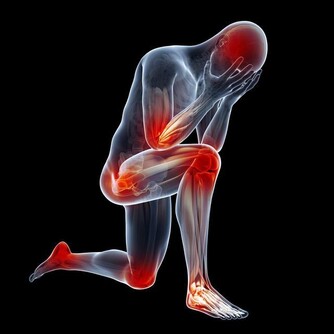

如果小腸受盛、化物的功能失調,那麼人體會出現腹脹、腹痛,或者是腹瀉、便溏。

如果大腸傳導失司,則會導致排便異常。

若大腸濕熱,氣機阻滯,則會肚子痛、拉肚子、大便困難伴有大便拉不干淨的感覺,嚴重者大便有膿帶血。

若大腸實熱,則腸液乾枯而便秘;若大腸虛寒,則水穀雜下,腸鳴泄瀉。